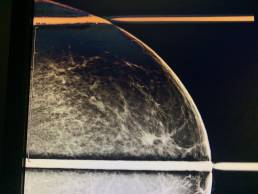

Femme de 54 ans, mammographie systématique de dépistage.

MammoScreen™ pointe une opacité rétromamelonnaire externe gauche.

Le cliché localisé confirme une lésion spiculée rétromamelonnaire externe.